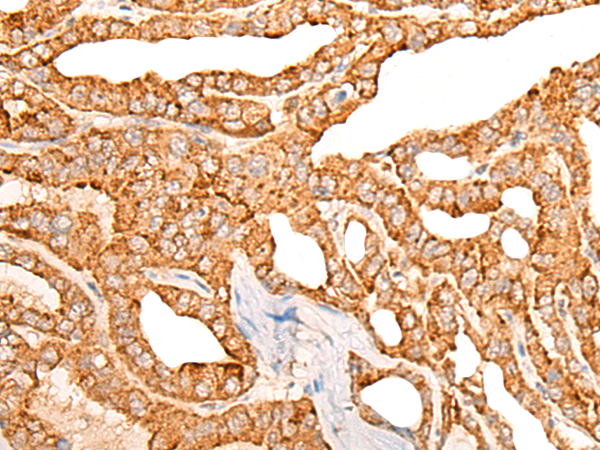

IHC positive control: |

Human thyroid cancer |